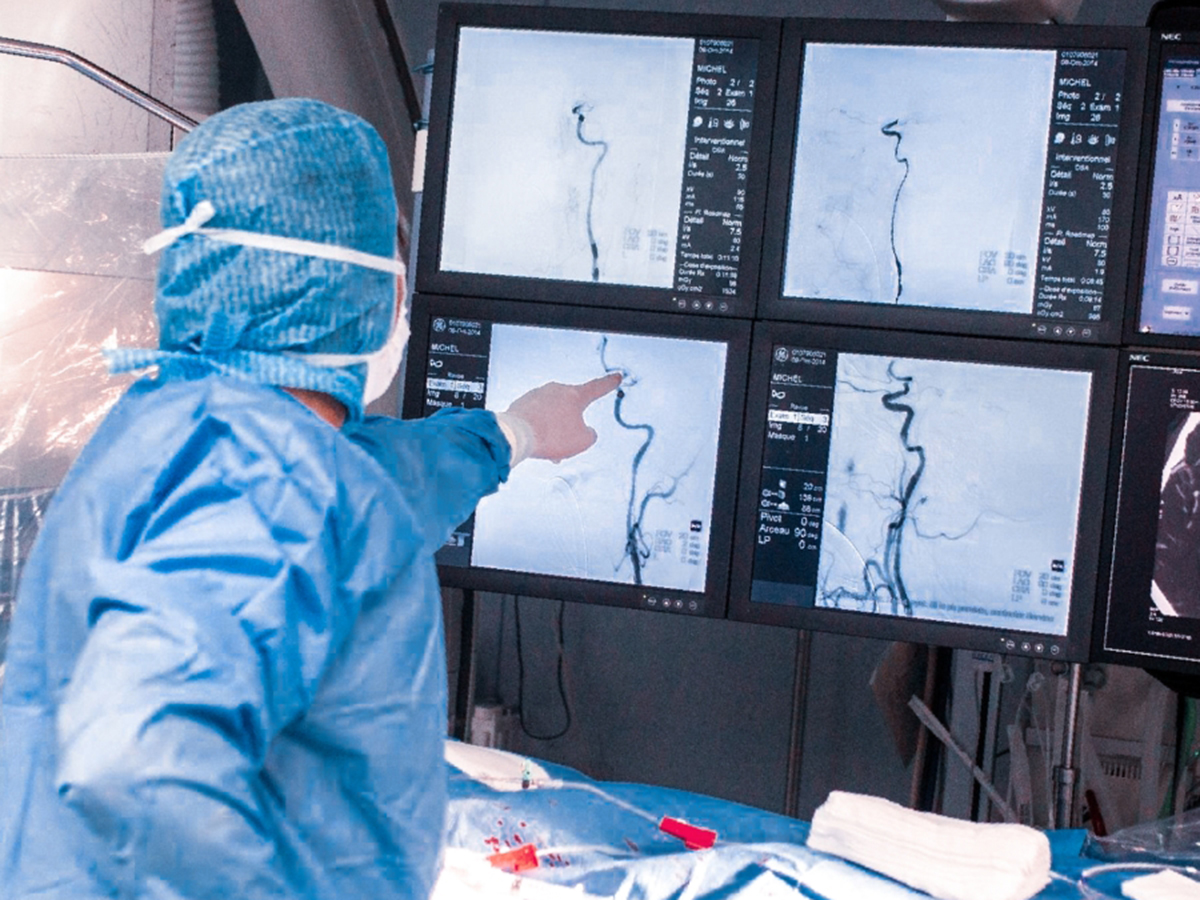

Хирургические процессы при эмболизации гемангиомы на фото

Раздел: Снимки-откровения